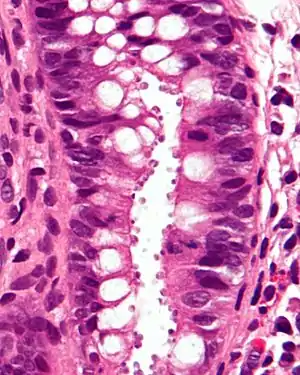

| Micrograph showing cryptosporidiosis. The cryptosporidium are the small, round bodies in apical vacuoles on the surface of the epithelium. H&E stain. Colonic biopsy. | |

Other staining techniques include acid-fast staining,[25] which will stain the oocysts red.[24] One type of acid-fast stain is the Kinyoun stain.[20] Giemsa staining can also be performed.[21] Part of the small intestine can be stained with hematoxylin and eosin (H & E), which will show oocysts attached to the epithelial cells.[24]